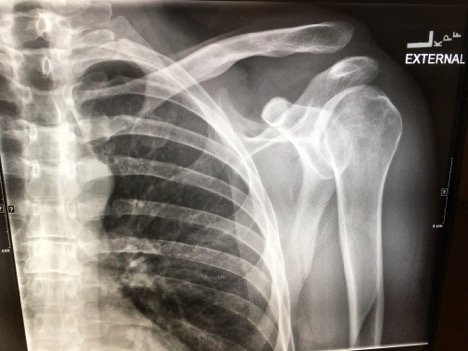

Plain films of the left shoulder showed elevation of the left clavicle above the acromion. There was an increase in the acromioclavicular (AC) and coracoclavicular (CC) distances (increased joint distances marked with red and blue arrows, respectively). A normal AC joint measures 1-3 mm whereas a normal CC distance measures 11-13 mm.1 The injury was classified as a Rockwood type III AC joint separation.

Initial evaluation with imaging includes plain films with three views: the anterior-posterior (AP) view with the shoulder in internal and external rotation as well as an axillary, or scapula-Y view (sensitivity 40%, specificity 90% for all films).6,7 AC joint injuries are classified by the Rockwood system.8 Type I involves a sprain or incomplete tear of the AC ligaments with an intact CC ligament. The AC joint appears normal on X-ray, but can become widened with stress, achieved by having the patient hold a 10-15 pound weight from each forearm.1,9 Type II injuries involve a torn AC ligament, disrupting the AC joint. The AC joint appears widened on radiographs.1,9 The AC and CC ligaments are disrupted in type III injuries with an increased CC distance of 25%-100% on plain films.1,10 In addition to torn AC and CC ligaments, the clavicle is posteriorly displaced in a type IV injury. Because the AP film may not reveal the posterior displacement of the clavicle, the axillary view is vital for correct classification of type IV injuries.1 A type V injury involves disruption of the AC and CC ligaments as well as torn muscle attachments of the trapezius and deltoid on the clavicle and scapula, leading to greater AC joint displacement on radiographs. The CC distance appears 100%-300% greater than normal.1,10 Type VI injuries are caused by a direct blow to the superior surface of the clavicle resulting in inferior displacement. On X-ray, the lateral end of the clavicle is inferior to the acromion and coracoid processes in Type VI injuries.1